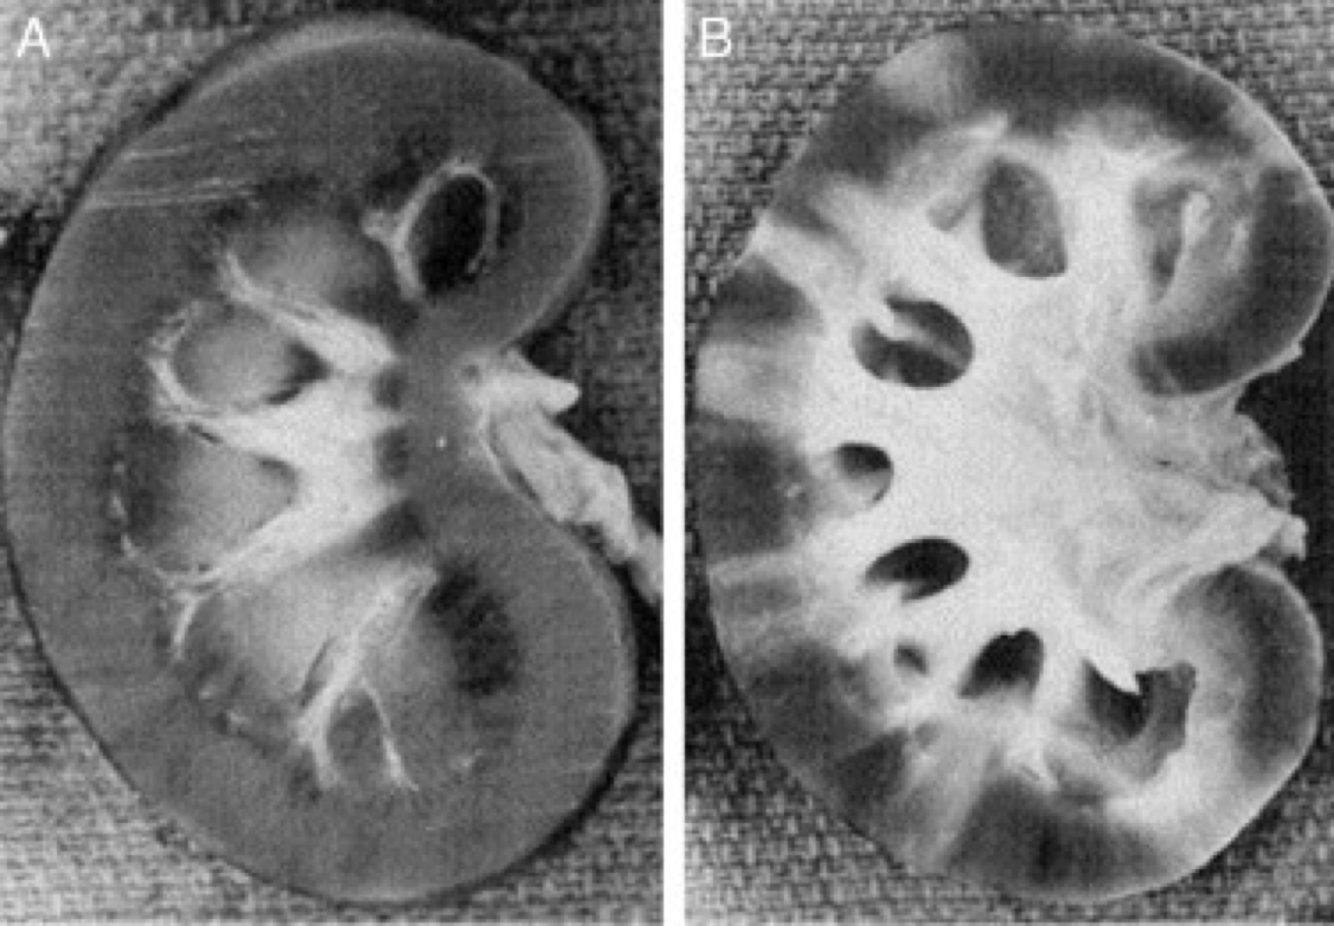

Normal kidney on the left. What is wrong with the left?

Scars. Could be from pyelonephritis, infarct, etc. Need biopsy

Acute pyeolonephritis can lead to chronic pyelonephritis. What are some of the problems that can occur?

scarring and fibrosis

tubular atrophy and “thyroidization”

leads to hypertension (RBF is 20% of CO)

leads to chronic renal failure